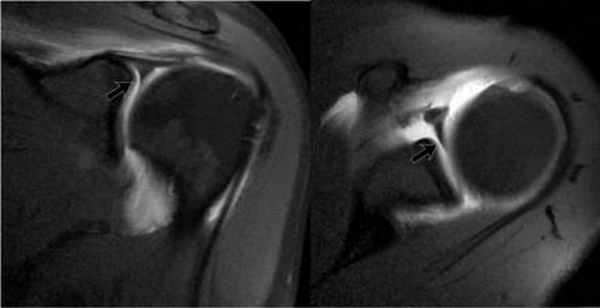

Передне-задняя артрограмма плеча, ротированного кнаружи: визуализируется нормальный косой контур прикрепления капсулы к анатомической шейке плечевой кости. Распространение контраста латеральнее данной линии и/или латеральнее большого бугорка указывает на разрыв вращательной манжеты. Обратите внимание на нормальное заполнение кармана двуглавой мышцы и подмышечного кармана. Передне-задняя артрограмма плеча, ротированного внутрь: визуализируется контраст, заполняющий подлопаточный карман. Подлопаточный карман (иначе называемый сумкой) образует сумку, перекидывающуюся через верхний край подлопаточной мышцы. Свободные тела часто мигрируют в нее или в подмышечный карман. Рисунок, вид спереди: показаны взаимоотношения мышц-вращателей плеча и интервала вращателей—участка треугольной формы, расширяющегося медиально и сужающегося латерально, с вершиной у переднего края большого бугорка. Показано сагиттальное сечение внутрисуставной части области плеча, удалена головка плечевой кости. Верхняя и средняя суставно-плечевая связки берут свое начало рядом с сухожилием двуглавой мыщцы, но верхняя суставно-плечевая связка имеет горизонтальное направление и образует часть петли сухожилия двуглавой мышцы. Средняя суставно-плечевая связка имеет косое нижнелатеральное направление и обеспечивает стабильность передней части. Пучки нижней суставно-плечевой связки берут свое начало около экватора суставной впадины лопатки спереди и сзади и образуют переднюю и заднюю границы подмышечного кармана. Схематично оказана нормальная анатомия интервала вращателей. Поперечные сечения в латеральной, средней и медиальной частях интервала вращателей представлены вдоль нижней части изображения. У латеральной части интервала, сразу проксимальнее входа в межбугорковую борозду плечевой кости, медиальный пучок клювовидно-плечевой связки (голубой цвет) и верхняя суставно-плечевая связка образуют петлю вокруг сухожилия длинной головки двуглавой мышцы. В средней части интервала вращателей клювовидно-плечевая связка покрывает верхнюю поверхность сухожилия двуглавой мышцы, а верхняя суставно-плечевая связка образует Т-образное соединение с клювовидно-плечевой связкой. Около медиального края интервала вращателей верхняя суставно-плечевая связка представляет собой округлую структуру, лежащую кпереди от сухожилия двуглавой мышцы; обе структуры покрыты U-образной клювовидно-плечевой связкой. Первая из шести выбранных косых корональных Т1ВИ МР-артрограмм, полученных вдоль оси сухожилия надостной мышцы. Задний пучок нижней суставно-плечевой связки образует толстый, четко различимый пучок по заднему краю подмышечного кармана. Задневерхняя губа суставной впадины лопатки часто имеет немного более высокую интенсивность сигнала, чем остальная часть, вероятно, вследствие артефакта «магического угла». Обратите внимание, что у этого пациента 20 лет в диафизе плечевой кости в первую очередь визуализируется кроветворный костный мозг, в то время как эпифиз содержит преимущественно желтый костный мозг. Очаги кроветворного костного мозга в диафизе плечевой кости сохраняются на протяжении всей жизни и могут быть ошибочно приняты за патологическое замещение. Кзади от начала двуглавой мышцы верхняя губа плотно прилежит к нижележащему суставному хрящу. Подмышечный карман четко очерчен и выступает за нижний край суставной впадины лопатки к шейке плечевой кости. Двуглавая мышца берет свое начало у надсуставного бугорка лопатки и крепится к верхней губе, затем следует латерально и кпереди над головкой плечевой кости и входите межбугорковую борозду плечевой кости. Визуализация места прикрепления длинной головки двуглавой мышцы плеча к суставной губе может различаться в зависимости от ротации плеча. В этом случае плечо ротировано кнаружи и проксимальная часть двуглавой мышцы располагается практически параллельно к плоскости визуализации. Трехстороннее отверстие визуализируется между сухожилием двуглавой мышцы и верхней губой. Эту находку кпереди от места прикрепления длинной головки двуглавой мышцы плеча к суставной губе не следует путать с повреждением верхней суставной губы лопатки спереди назад. Обратите внимание на нормальное распределение внутрисуставного контраста вдоль влагалища сухожилия двуглавой мышцы. Как правило, в передней проекции сустава визуализируется подлопаточный карман, выступающий над верхним краем подлопаточной мышцы. Обратите внимание на нормальное соединение сухожилия подлопаточной мышцы и самой мышцы. Также визуализируется наиболее передняя часть клювовидно-плечевой связки, сливающаяся с латеральными волокнами подлопаточной мышцы. На первой из шести отобранных Т1 FS МР-артрограмм визуализируется плечевой сустав в направлении сверху вниз. Сухожилие двуглавой мышцы проходит над головкой плечевой кости. Клювовидно-суставная связка визуализируется частично, сплетаясь с клювовидно-плечевой связкой. Клювовидно-плечевая связка имеет средний пучок, который образует часть петли сухожилия двуглавой мышцы, и латеральный пучок, который перекидывается через передний край подлопаточной мышцы и крепится к подлопаточной мышце, а также к малому и большому бугоркам, формируя таким образом часть поперечной связки. В литературе обсуждается вопрос, является ли поперечная связка самостоятельной структурой. Она представляет собой слияние волокон подлопаточной мышцы и петли сухожилия двуглавой мышцы, удерживает сухожилие двуглавой мышцы в межбугорковой борозде. Передняя и задняя губы прилежат к хрящу на передней поверхности суставной впадины. Задняя губа не имеет сублабральной борозды и жидкость между суставным хрящом и губой всегда наблюдается в норме. Средняя суставно-плечевая связка прилежит к заднему краю сухожилия подлопаточной мышцы, с которым сливается в нижней части. Площадка истонченного хряща суставной впадины лопатки в норме расположена центрально и известна как «голая зона». Здесь часто располагаются выступающие кровеносные сосуды кзади от головки плечевой кости, которые иногда ошибочно принимают за субхондральные кисты. Анализ округлых участков на последовательных снимках поможет установить их тубулярное строение, что соответствует сосудистым структурам. При визуализации места прикрепления передней части капсулы сустава к лопатке отмечается значительная вариабельность. В норме в данной области глубже подлопаточной мышцы наблюдается небольшой карман. Подмышечная петля состоит из множества пучков с участками небольшого расхождения между ними. Это создает слоистый вид в месте их прикрепления к шейке плечевой кости. Обратите внимание, что хотя верхняя часть подлопаточной мышцы фиксирована к плечу посредством сухожилия, нижняя-крепится посредством мышечной ткани. Первая из девяти отобранных сагиттальных PD FS МР-артрограмм, от латеральной к медиальной: визуализируется нормальная вращательная манжета в виде кольца по типу велосипедной шины вокруг верхней и задней поверхностей головки плечевой кости. Небольшие разрывы сухожилия надостной мышцы часто возникают в переднем или «ведущем» крае, который лучше визуализируется в сагиттальной проекции. Обратите внимание на высокоинтенсивный сигнал в области дельтовидной мышцы, отражающий наличие лидокаина, введенного во время процедуры. Последовательность PD FS позволяет визуализировать контрастное вещество и другие жидкости с высокоинтенсивным сигналом. Визуализируется подлопаточная мышца, которая прикрепляется к малому бугорку. Сухожилие двуглавой мышцы находится сразу выше данного участка при изгибе и вступлении в межбугорковую борозду. Клювовидно-плечевая связка лежит выше двуглавой; она и поверхностные волокна подлопаточной мышцы сливаются, образуя поперечную связку межбугорковой борозды. Сагиттальная плоскость лучше подходит для оценки внутрисуставного расположения сухожилия двуглавой мышцы, поскольку эффект частичного объема затрудняет точную визуализацию в корональной и аксиальной плоскостях. Обратите внимание, что подлопаточная мышца имеет множественные сухожильные волокна, чередующиеся с мышечными, а нижняя треть- мышечное прикрепление к малому бугорку. На этом уровне начинает визуализироваться подлопаточный карман, простирающийся над верхним краем подлопаточной мышцы. Передний и задний пучки нижней суставно-плечевой связки определяются в месте прикрепления к хирургической шейке плечевой кости. Клювовидно-плечевая связка представлена широким пластом и делится на медиальный и латеральный пучки. Подмышечный карман имеет множество пучков, что создает исчерченный вид. Клювовидно-плечевая связка заполняет интервал вращателей и перекидывается через верхнюю часть сухожилия двуглавой мышцы. Латеральный пучок визуализируется в месте прикрепления к переднему краю подлопаточной мышцы. Клювовидно-плечевая связка и клювовидно-суставной пучок визуализируются в месте их начала у основания клювовидного отростка. Их визуализация в значительной степени вариабельна. В норме визуализируются множественные карманы сустава: подмышечный, задний и подлопаточный (часто именуемый подлопаточной сумкой). Снимок получен медиальнее предыдущего, но у другого пациента; вследствие большего растяжения полости сустава достигнута лучшая визуализация карманов сустава и суставно-плечевых связок. Суставная губа визуализируется частично. Хотя сагиттальный срез не является первостепенным для оценки губы, на этом уровне наличие контрастного вещества между костью и губой подтверждает разрыв губы. На аксиальной Т1 МР-артрограмме визуализируется сублабральное окно. Этот вариант нормы имеет место в передневерхнем квадранте губы, где редко возникают изолированные разрывы губы. Они не распространяются ниже уровня клювовидного отростка. В отличие от неровного зазубренного контура при разрыве губы, сублабральное окно имеет ровный контур. На аксиальной Т1 МР-артрограмме визуализируется сублабральное окно (другой пациент). Снимки получены ниже для дифференцировки между губой и сублабральным окном (в этом случае верхняя губа присоединяется к кости более низко) или комплексом Буфорда (в этом случае тяжистая средняя суставно-плечевая связка сливается с подлопаточной мышцей и отдельная верхняя губа визуализируется более низко). Артроскопия: визуализируется прочно прикрепленная суставная губа кзади от места прикрепления длинной головки двуглавой мышцы плеча к суставной губе и сублабральное окно в передневерхнем квадранте сустава. На рисунке в сагиттальной плоскости показан комплекс Буфорда: передняя верхняя суставная губа отсутствует, средняя суставно-плечевая связка утолщена и натянута. На аксиальной Т1 FS МР-артрограмме визуализируется комплекс Буфорда. Средняя суставно-плечевая связка утолщена и натянута. Такое строение может быть немного нестабильным, так как пациенты с комплексом Буфорда имеют повышенный риск повреждения верхней суставной губы лопатки спереди назад. На аксиальной Т1 FS МР-артрограмме у пациента с комплексом Буфорда на этом уровне определяется наличие губы, средняя суставно-плечевая связка остается натянутой.

Комплекс Буфорда

Комплекс Буфорда это врожденный вариант строения суставной губы в виде отсутствия ее передневерхних отделов в области на 1-3 часа и утолщение средней плече-лопаточной связки.

Определяется в 1,5 % случаев.

На аксиальных изображениях слева может быть виден комплекс Буфорда.

Отсутствуют переднеие отделы суставной губы в области на 1-3 часв, утолщена средняя плече-лопаточная связка.

Утолщенная средняя плече-лопаточная связка не должна обшибочно приниматься за смещенную суставную губу.

Всегда по возможности необходимо прослеживать ход средней плече-лопаточная связки сверху вниз от фиброзно-хрящевой губы гленоида к плечевой кости.